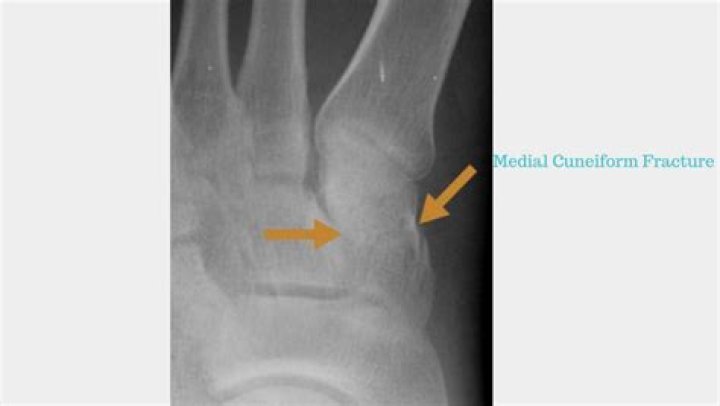

Isolated fractures of the cuneiforms are extremely rare, accounting for only 1.7% of all midfoot fractures.

How long does a cuneiform fracture take to heal?

There are three cuneiform ("wedge-shaped") bones in the human foot: the first or medial cuneiform. the second or intermediate cuneiform, also known as the middle cuneiform. the third or lateral cuneiform.